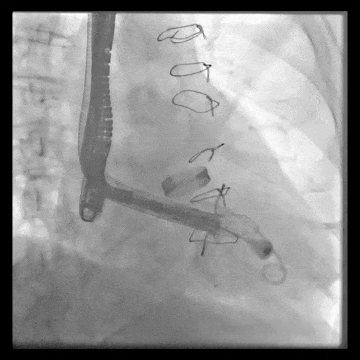

術(shù)后DSA